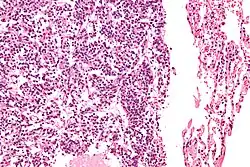

| Micrograph of a typical pulmonary carcinoid tumour. | |

The definitive diagnosis is rendered by a microscopic examination, after excision. Typical carcinoids have cells with stippled chromatin and a moderate quantity of cytoplasm. They typically have few mitoses and lack necrosis. By definition, they are greater than 4 mm in largest dimension; smaller lesions are referred to as pulmonary carcinoid tumourlets.